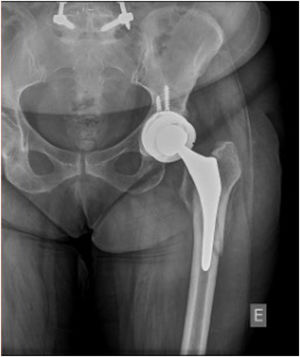

El 71% de los pacientes con fractura de GT tuvieron al menos un episodio de inestabilidad (p=0,008) (tabla 4 y fig. 3). El hecho de si la fractura de GT se fijó o no, así como el tipo de fijación, no revelaron diferencias en cuanto a la tasa de inestabilidad (p>0,05).

La presencia de fractura del trocánter mayor fue una variable clave de la inestabilidad, teniendo el 71,4% de los pacientes con dicha fractura al menos un episodio de la misma (p=0,008). De manera interesante, la realización de osteosíntesis de GT y los diversos tipos de osteosíntesis no revelaron diferencias en cuanto al tipo de inestabilidad (p>0,05). A pesar de que la fractura de GT es un factor de inestabilidad bien establecido11,30, este hallazgo aporta una significación ominosa a esta lesión (fig. 4). La osteosíntesis de la fractura de GT es a menudo difícil, debido al desplazamiento de la fractura por la tracción de los músculos del glúteo30 y al pobre stock óseo, ya que a menudo dichas fracturas están asociadas a osteólisis11.

La revisión de la copa acetabular no fue realizada en la cirugía índice, lo cual puede explicar aún más las tasas de inestabilidad más altas. El desgaste excéntrico del polietileno está asociado a osteólisis y aflojamiento aséptico31, pudiendo contribuir a inestabilidad. Tampoco se corrigió la posición del componente acetabular.